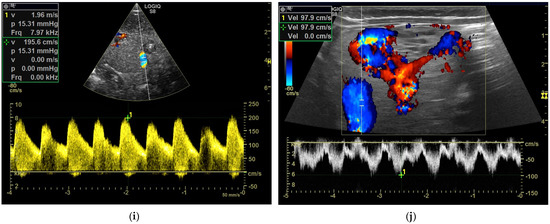

CEUS: CEUS characteristic of pediatric HEHE can refer to the experience of adult groups. During the arterial phase of CEUS, HEHE may show peripheral rim-like or heterogeneous hyperenhancement. In the portal venous phase and late phase, HEHE shows quick washout and becomes hypoenhanced with unenhanced central areas [66,67]. Typical CEUS imaging features reliably allow for effective differentiation between HEHE and other benign FLLs such as hepatic hemangioma and FNH, both showing hyperenhancement and remaining iso- or hyperenhanced in the portal venous and late phase [63] (Figure 3).

Figure 3.

Hemangioendothelioma in a 1-month-old infant. A cystic mass with a maximum diameter of 4 cm in liver segment IV with blurred borders and calcifications with dorsal acoustic shadow (a–e). Evidence of increased vascularization on color Doppler (f). Feeder artery with inflow from the hepatic artery and venous outflow via the markedly dilated left hepatic vein (g). Increased flow velocities in the coeliac trunk and hepatic artery (h,i). Outflowing left hepatic vein with arterialized flow profile and increased flow velocities (j).